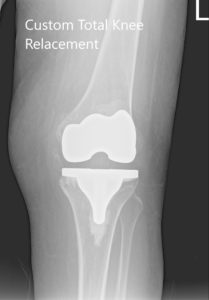

IMPLANTES UTILIZADOS: Personalizado fémur y tibia bilateralmente, con polietileno de 10 mm bilateralmente. Rótula derecha 29 mm x 6 mm y rótula izquierda 32 mm x 6 mm.

Radiografía postoperatoria que muestra AP y vistas laterales de la articulación de la rodilla derecha e izquierda.